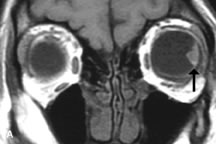

On MRI, uveal melanomas have a typical appearance that helps to differentiate them from other primary and secondary intraocular tumors as well as choroidal detachments. Pigmented melanomas are hyperintense on Tl-weighted images, hypointense on T2-weighted studies, and hyperintense on proton density–weighted examinations (Fig. 24).30,31,50,80–82 These signal characteristics have been attributed to the paramagnetic properties of melanin because of stable free radicals that shorten the T1 and T2 relaxation times. Moderate enhancement is seen on postgadolinium T2-weighted images. Gadolinium-enhanced T1-weighted images are particularly sensitive in detecting choroidal melanomas.83 MRI may be less sensitive in detecting extrascleral extension of tumor than echography performed by an experienced ultrasonographer.84

Fig. 24. A. T1- and (B) T2-weighted MR scans demonstrate a small nodular intraocular mass (arrows) that is very hyperintense on the T1-weighted scan and hypointense on the T2-weighted image. This signal intensity pattern is due to the presence of free radicals within melanin granules. C and D. Postcontrast fat-suppressed T1-weighted scans demonstrate homogeneous intense enhancement of the lesion and no evidence of seleral penetration or optic nerve invasion.